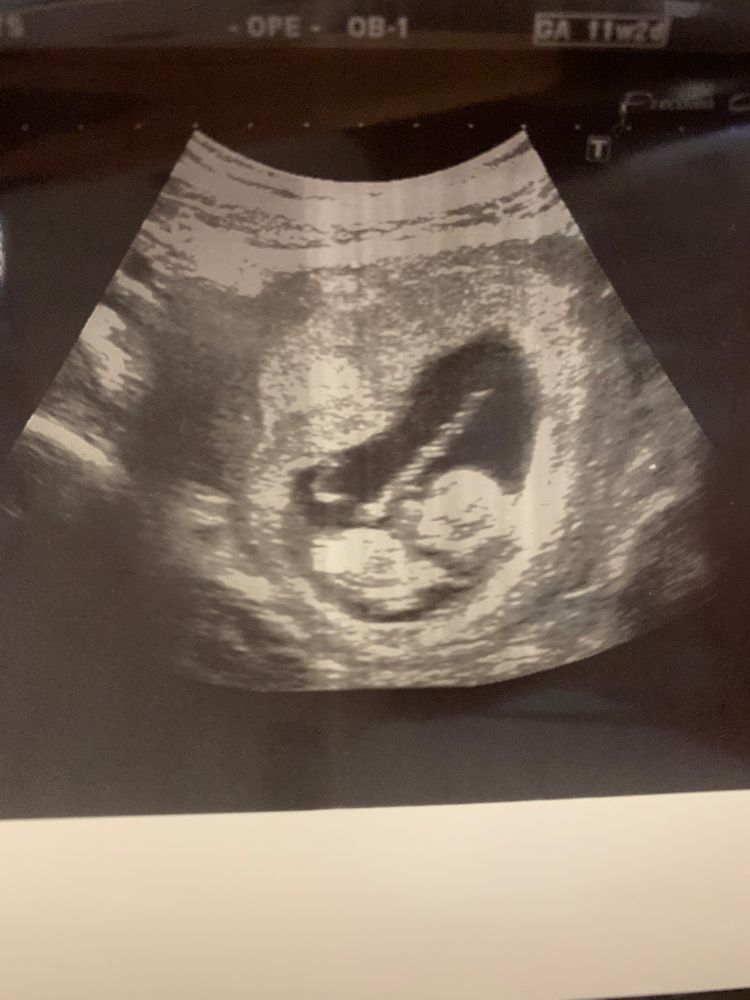

УЗИ, КТГ, доплер11 недель + 3 дня . На кого больше похоже?🙈 если, конечно , можно рассмотреть)

На первом фото похоже на мальчика, у меня в этот раз такой же был в 11 недель)

Я бы сказала вероятность девочки 50/50 😄 А вообще я делала скрининг на Вашем сроке, потом переделывала узи в 13 недель из-за проблем, вот в 13 недель бугорок уже был хорошо поднят вверх, сомнений оставалось мало, если будете делать позже узи там будет яснее, бугорок либо поднимется, либо останется прямой))

На таком сроке половой бугорок выглядит одинаково у девочек и мальчиков, только небольшая разность угла наклона и не на 100% может указывать на пол, но только на хорошем аппарате и опытный узист🤷♀️